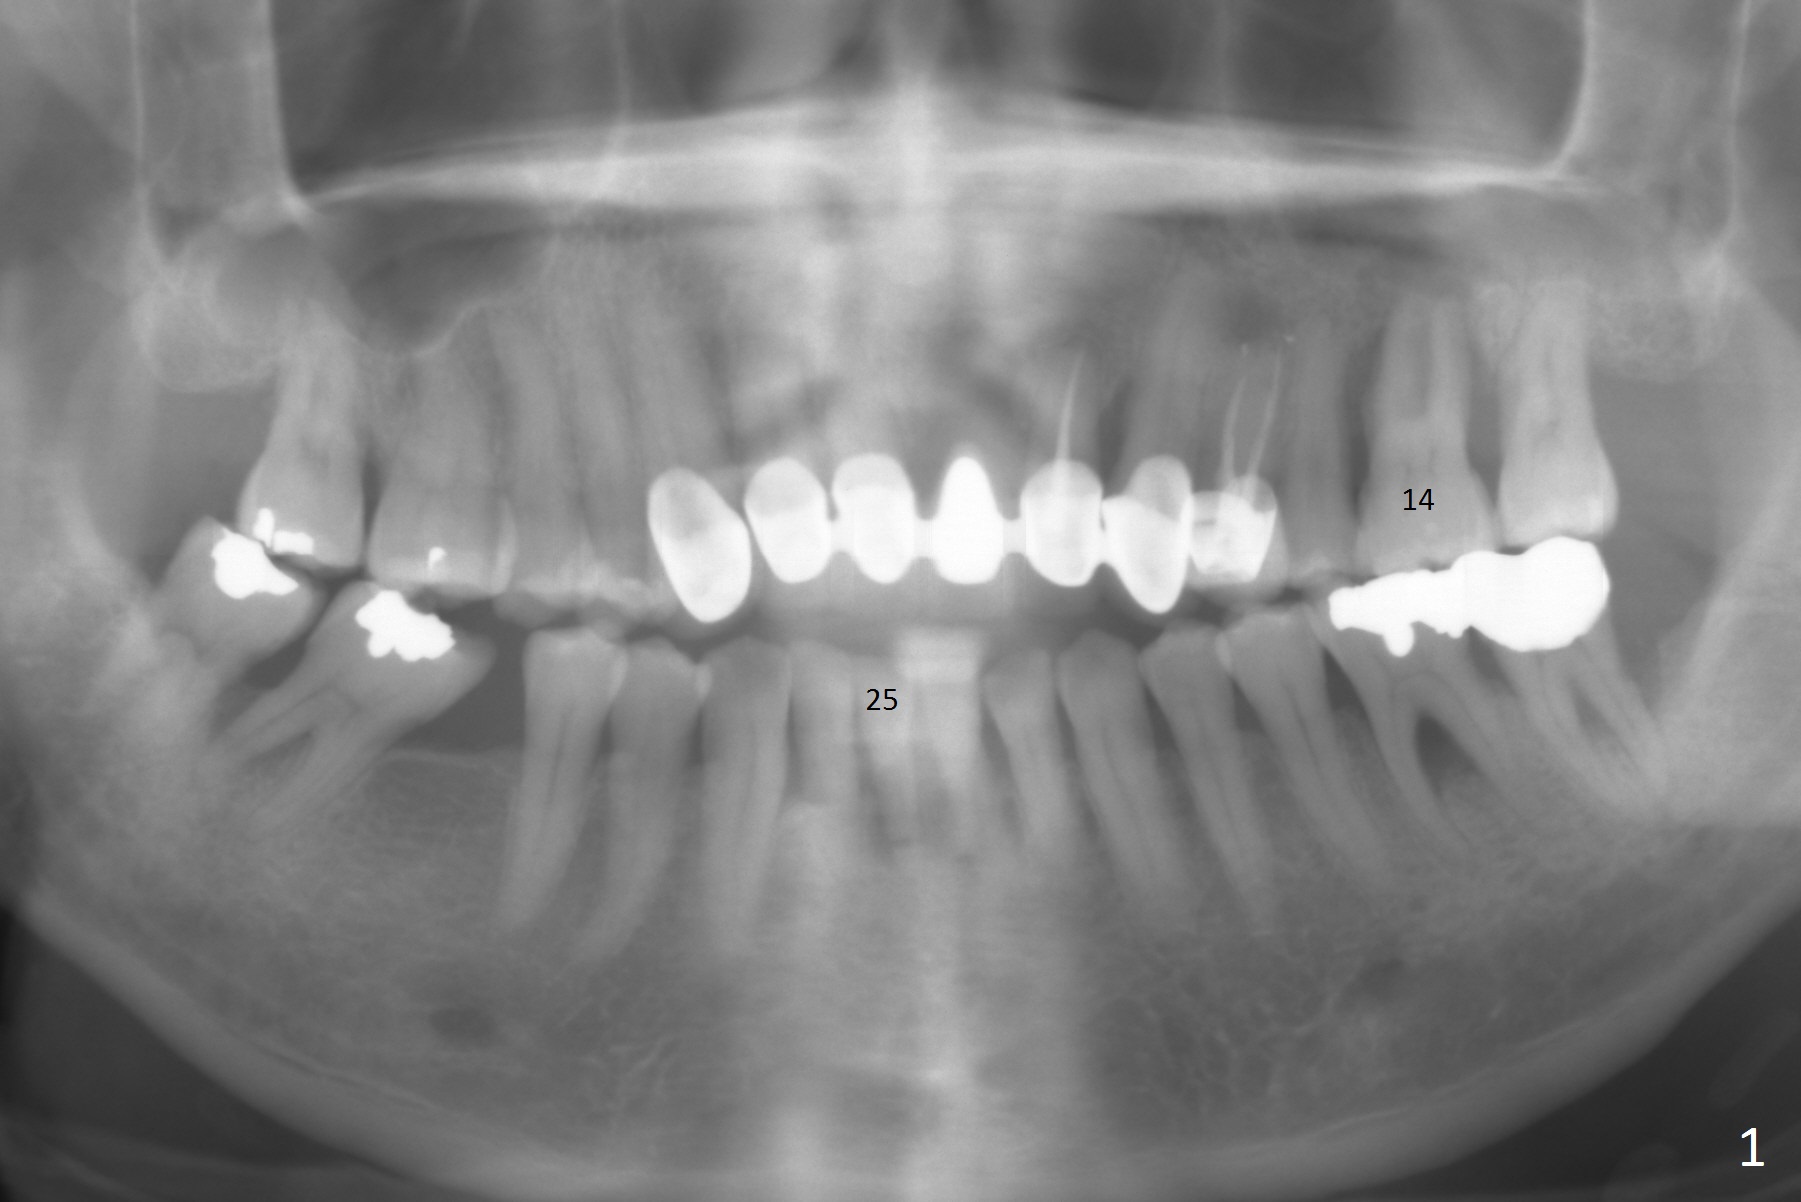

A 48-year-old man is determined to have implants for mobile teeth #14 and 25 (Fig.1).  He is not pleased with the upper anterior FPD because of difficulty in cleaning.  In addition to severe gingival recession (Fig.2), there is an abscess lingual to the tooth #25 (Fig.3).   The latter should be associated with lingual plate defect.  Osteotomy should be initiated in the center of the socket, in contrast to usual lingual starting point.  A 3x16(4) mm 1-piece implant is to be placed unless the socket is small buccolingually or mesiodistally.  Take PA immediately after his arrival for surgery to determine the mesiodistal width and the gingival thickness.  The 2nd parameter will decide what parameter of the implant?